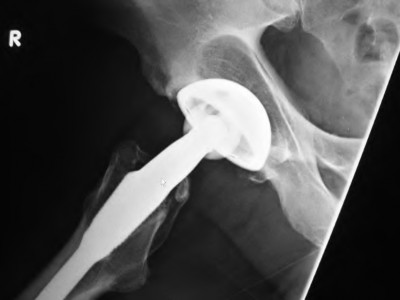

A 72-year-old female falls and sustains a periprosthetic femur fracture around her cementless total hip arthroplasty. Radiographs reveal a fracture extending just distal to the tip of the stem. The stem is radiographically loose, but there is excellent proximal and distal bone stock. According to the Vancouver classification, what is the fracture type and the recommended surgical treatment?

Explanation